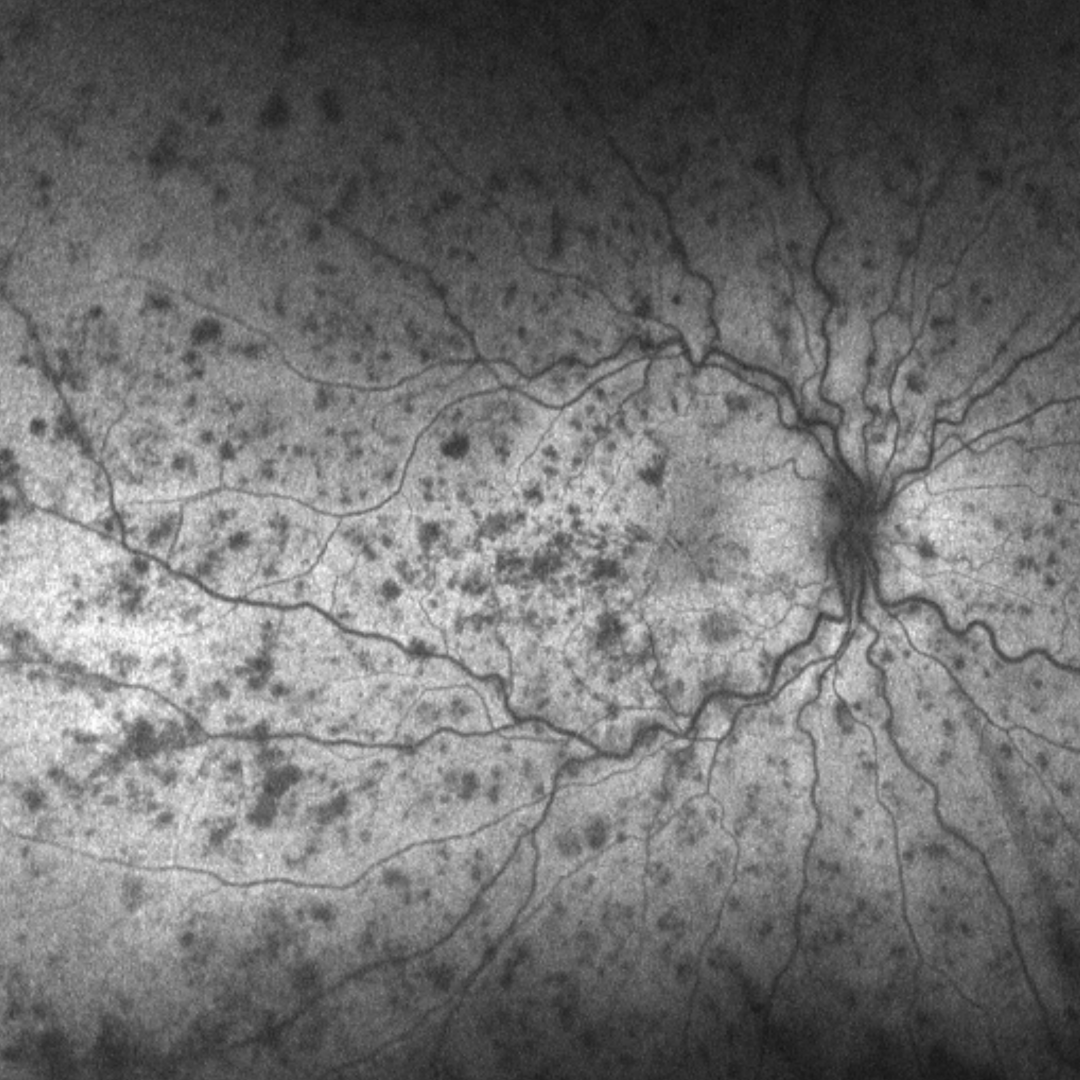

Neovascularisation can be a challenge to identify on retinal photography as the vessels as the vessels are typically very fine and thin (1). A red-free filter (or green separation widefield image) may help in identifying these vessels (2).

The presence or otherwise of cotton wool spots is not an accurate indicator of the ischaemic nature of a venous occlusion. Fluorescein angiography is required to determine whether an occlusion is ischaemic or not.